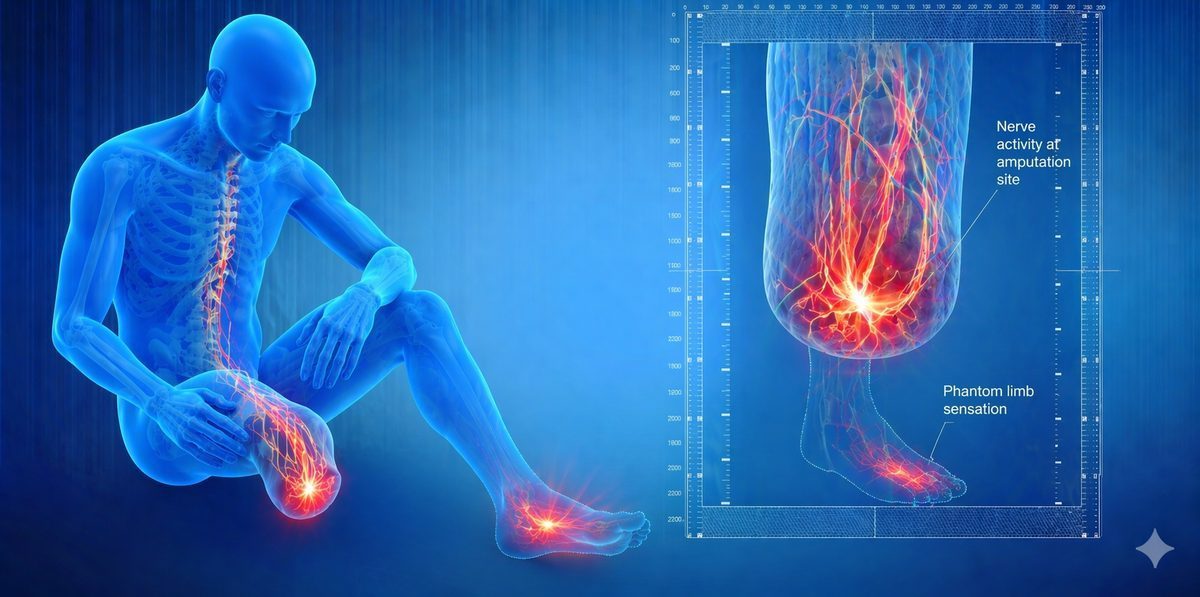

Illustration showing pain pathways in the brain and spinal cord related to phantom limb pain

The brain maps every part of the body in a region called the somatosensory cortex. After amputation, the nerves from the missing limb no longer send normal signals. The brain interprets this as pain. Over time, something called cortical reorganisation can make the problem worse. Nearby body parts begin to take over the brain area that used to represent the missing limb, and this remapping drives ongoing pain signals.

Phantom limb pain is different from phantom sensation, which is simply the feeling that the limb is still there without pain. Both are common after amputation. Pain affects up to 80% of amputees to some degree.

Illustration showing neuroma formation in a residual stump and phantom limb pain pathways

1. Central Sensitisation: The spinal cord and brain become hypersensitive after amputation. Pain signals are amplified even when the original stimulus is no longer present. This is one of the main drivers of phantom pain.

2. Peripheral Nerve Activity: The cut ends of nerves in the stump continue to fire abnormal electrical signals. These signals travel up to the brain and are interpreted as coming from the missing limb.

3. Cortical Reorganisation: The brain area that used to receive signals from the amputated limb starts to be taken over by neighbouring areas. This reorganisation is associated with increased phantom pain intensity.